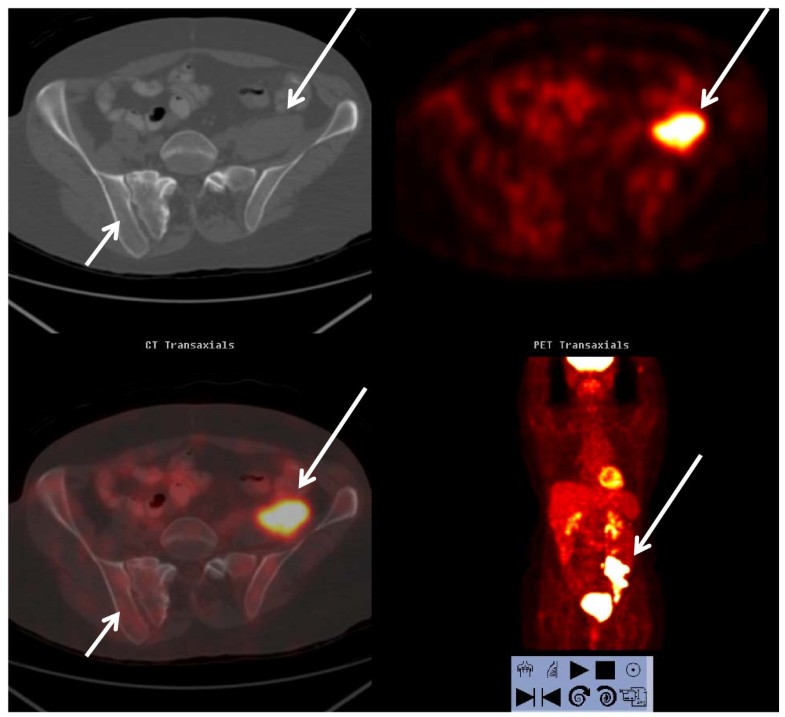

From bmccancer.biomedcentral.com

Does colon cancer ever metastasize to bone first? a temporal analysis Does Colon Cancer Affect Bones Cancer that starts in one part of the body and spreads to the bone is called bone metastases. Bone metastasis may be the first sign that you have cancer, or bone metastasis may occur years after cancer treatment. It's sometimes called secondary bone cancer. Bone metastasis is a symptom of metastatic cancer that happens when cancer from one place in. Does Colon Cancer Affect Bones.

Does colon cancer ever metastasize to bone first? a temporal analysis Does Colon Cancer Affect Bones Bone metastasis may be the first sign that you have cancer, or bone metastasis may occur years after cancer treatment. Cancer cells can spread from the colon or rectum to other parts of the body. Bone metastasis is a symptom of metastatic cancer that happens when cancer from one place in your body spreads to your bones. But they can. Does Colon Cancer Affect Bones.